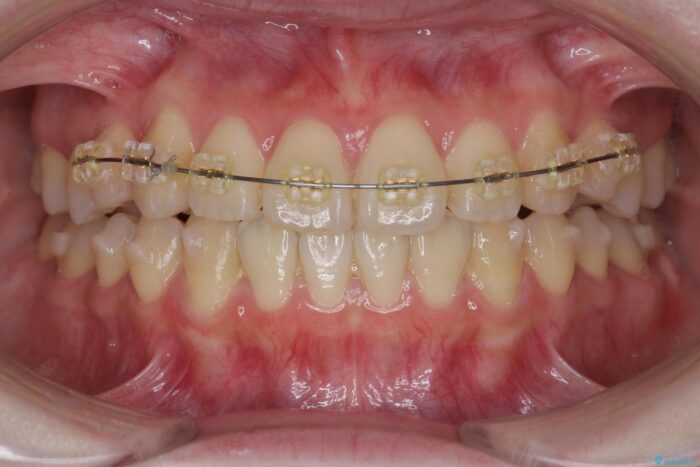

インビザライン +部分ワイヤー矯正

歯のねじれをきれいに取るのは、インビザライン(マウスピース矯正)だけでは難しい動きです。そのため、事前に4か月間の部分ワイヤー矯正を行い、治療期間を短くし、より美しい仕上がりを目指す計画です。

前歯が綺麗に並び、大変ご満足いただけました。